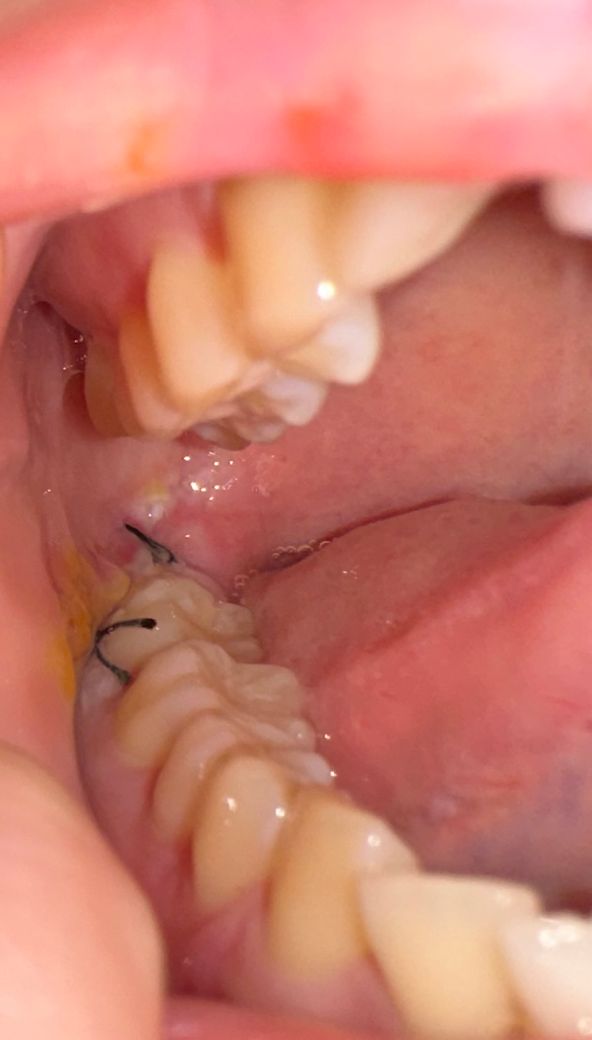

매복사랑니발치6일차.. 혹시 이거 드라이소켓인가요 ?̊̈. 고름찬거 같은데

지금 신경쪽 가까운 매복사랑니 뽑은지 6일차인데 아직도 욱신거리고 아파요... 머리가 살짝 울리듯이 아파서 방금 또 약을 먹긴 했는데 아직도 볼쪽이 멍울이 있어서 불편한데.. 왜 저렇게 볼쪽에 노란거랑 흰색이 있는거죠 ?̊̈..염증인건가요 ?̊̈ 아무는중인건가요.. 드라이소켓은아닌가요 ?̊̈.

드라이소켓은 아닌 것으로 보입니다. 살이 씹히거나 한 부분이 조금 있어보이며 크게 문제가 될 것 같진 않습니다.

현재 사진상 드라이소켓은 아닌 것으로 보이며, 발치부위 노란색, 흰색부분은 혈전위로 섬유조직이 차오르는 과정입니다. 회복되는 과정으로 정상이나 만약 해당부위가 점점더 통증이 심하거나 고름이 차거나 악취가 발생시에는 치과 진료를 권합니다.